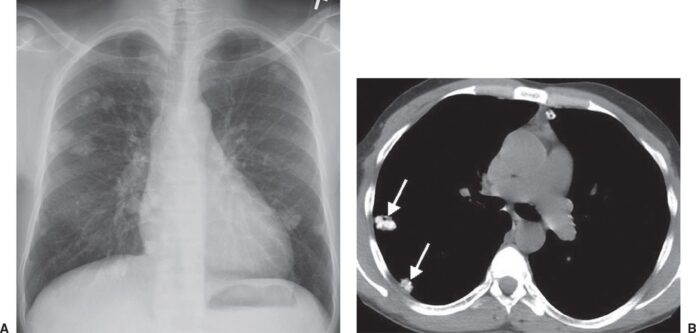

Multiple Lung nodules are often found on the chest X-rays of people with symptoms such as shortness of breath, cough, weight loss, or chest pain. They are usually benign (not cancerous) but must be checked out. Some lung nodules may need to be treated because they are cancerous. The best treatment depends on what type of nodule you have, how old you are, how big it is, and whether it has spread to other body parts. The size of a nodule doesn’t tell you what it is. Your doctor can usually figure that out by looking at it on an X-ray or CT scan. When cancer cells form in the tissue of your lungs, they can invade the walls of the air sacs (bronchi) that connect to the lungs. This invasion causes the bronchi to become blocked. The result is shortness of breath, coughing blood, fever, weight loss, and other symptoms. In most cases, lung cancer is diagnosed after it has spread beyond the lungs into nearby lymph nodes or other parts of the body.

Multiple lung nodules, sometimes called pulmonary nodules, are small, round growths on a chest X-ray. These growths are usually benign (noncancerous) but can also be cancerous. Most people who get a chest X-ray have at least one lung nodule. Sometimes, they’re small and hard to notice. Sometimes, they’re bigger and easier to spot. Lung nodules can be single or multiple or may be part of a larger pattern, like the “halo sign”, where a mass surrounds a lung tumor. Sometimes, lung nodules can be found on a chest CT scan, called pulmonary nodules or pulmonary metastases.